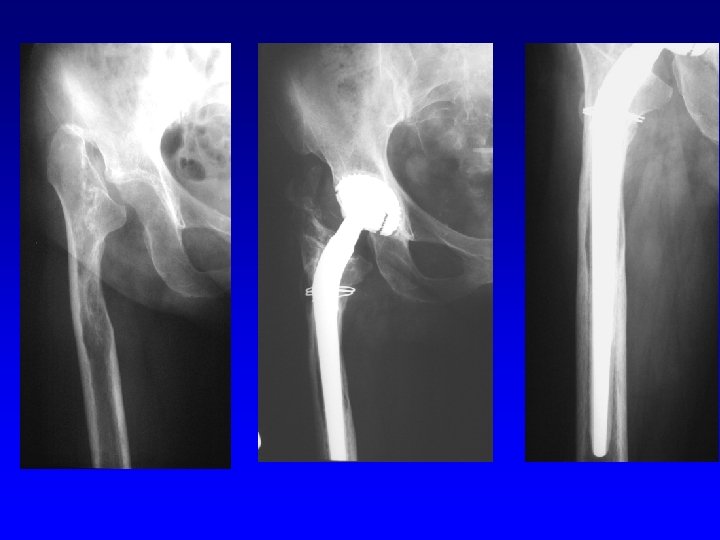

Indications Primary osteoarthrosis Secondary osteoarthrosis: congenital, posttraumatic, after infection Revmatoid arthritis Psoriatic arthropathy Avascular necrosis of the femoral head Primary osteoarthritis

For tumors

Revision THA

Revision of the acetabulum